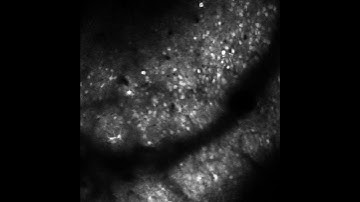

Intravital microscopy of the microcirculation in the mouse brain utilizing a sealed cranial window